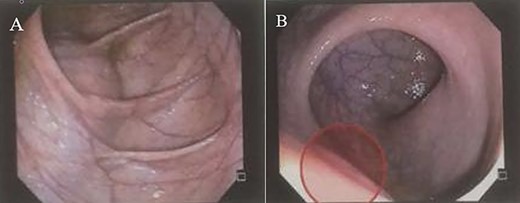

A 28-year-old female patient with a surgical history of excision of a pilonidal cyst 2 years ago presented with local discomfort when sitting for 6 months. The examinations performed suggested a tailgut cyst, and the principal differential diagnosis was a recurrence of the pilonidal cyst. Abdominal and pelvic MRI identified an extensive collection occupying soft tissues in the sacrococcygeal region, extending anteriorly under the sacrum and coccyx to the retrorectal space on a closed end, apparently without continuity with the subcutaneous mesh in the buttocks region. It had thin and regular walls and partial parietal enhancing of the rectosacrococcygeal portion, measuring 9.9 × 7.9 × 3.9 cm, with an estimated volume of 158 ml. The collection exerted a modest compressive effect on an adjacent posterior rectal wall but maintained a well-defined cleavage plane (Fig. 1). Colonoscopy showed extrinsic compression in the posterior and right lateral wall of the inferior rectum, above the puborectalis muscle (Fig. 2). Rectal ultrasonography showed multicystic content in the retrorectal space (Fig. 3). The patient underwent a complete resection of the tailgut cyst via posterior intergluteal access. She was discharged on the first postoperative day, with no complications or sequelae and no evidence of recurrence until 18 months of postoperative follow-up.

(A and B) Colonoscopy shows extrinsic compression on the rectum.